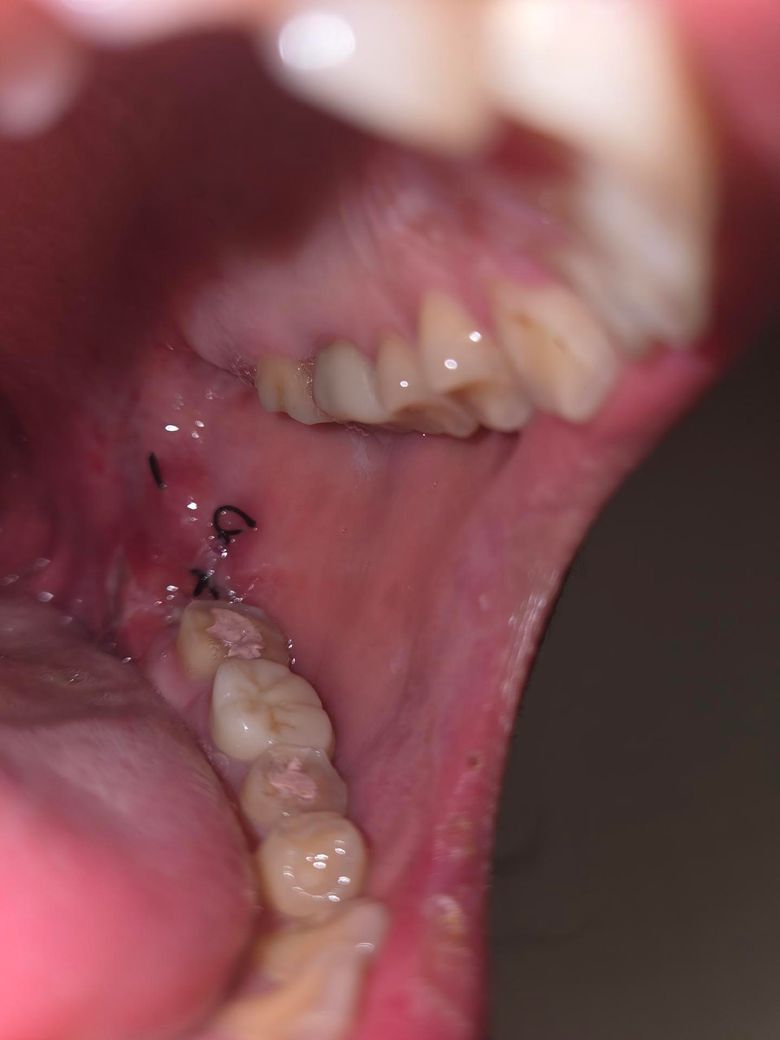

사랑니 양촉 매복을 발치 후 이상하게 잇몸 안쪽으로 하얀색으로 보이는게 있더라고요..통증도 있는데 이건 뭘까요?

드라이소켓일까요,

사진상으로 보면 사랑니 발치한곳이 잇몸이 아물면서 생기는 자연스러운 현상이니 너무 걱정하지마세요.

사랑니를 발치하는 과정에서 잇몸에 자극이 있다면 사진처럼 하얀색으로 보일 수 있습니다. 잇몸에 생긴 자극은 대부분 시간이 지나면서 줄어들기 때문에 너무 걱정하지 않아도 됩니다.

염증이 다소 생긴 것 같습니다. 발치 후 처방받은 항생제 약 남은거 있으면 복용하시고요. 드라이소켓의 양상은 아닙니다.